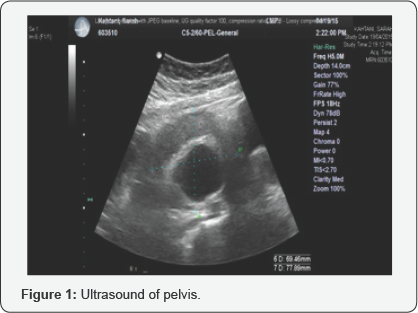

Pelvic US showed that the uterus was anteverted normal in size measures 62.56*22.85*31.92mm. Midline endometrial thickness was 5.49mm. Both ovaries were not seen. There was no free fluid within the pouch of douglas (P.O.D). Right adnexal mass was seen measured 70.42*70.48*78.64 mm, with cystic structure seen within it measures of 39.81*47.51mm, which could be dermoid cyst (Figure 1).